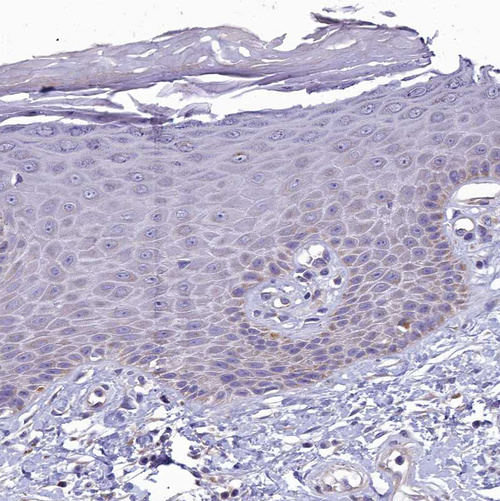

Immunohistochemical staining of human skeletal muscle shows strong cytoplasmic positivity in myocytes.